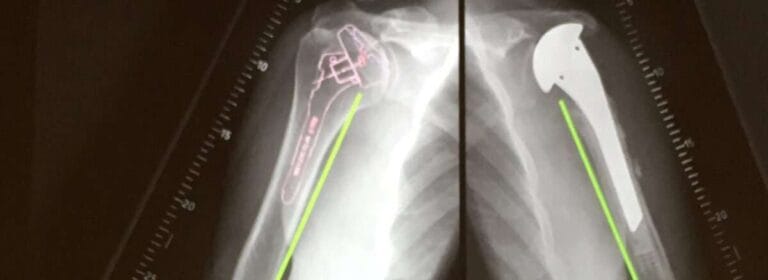

Shoulder Replacement

Ultimately in cases of severe non-resolvable pain or previously failed treatment options, shoulder replacement (arthroplasty) is indicated. There are several variations of shoulder replacements available, some more invasive than others. The choice of replacement depends on several criteria. These include age, activity level, a form of arthritis, and the amount of bone affected.

Arthroplasty Options

Hemiarthroplasty

Hemiarthroplasty involves a prosthetic metal implant being placed into the upper bone in the arm (humerus) which forms half of the shoulder joint. Whilst in total shoulder arthroplasty both sides of the joint are replaced. Depending on the condition of your shoulder, your surgeon may replace only the ball. This procedure is called a hemiarthroplasty. In a traditional hemiarthroplasty, the head of the humerus is replaced with a metal ball and stem, similar to the component used in a total shoulder replacement. This is called a stemmed hemiarthroplasty.

Resurfacing Hemiarthroplasty

Resurfacing hemiarthroplasty involves replacing just the joint surface of the humeral head with a cap-like prosthesis without a stem. With its bone preserving advantage, it offers those with arthritis of the shoulder an alternative to the standard stemmed shoulder replacement.

Total Shoulder replacement

The typical total shoulder replacement involves replacing the arthritic joint surfaces with a highly polished metal ball attached to a stem and a plastic socket. Patients with bone-on-bone osteoarthritis and intact rotator cuff tendons are generally good candidates for conventional total shoulder replacement.

Reverse Shoulder Replacement

Another type of shoulder replacement is called reverse total shoulder replacement. Reverse total shoulder replacement is used for people who have:

• Completely torn rotator cuffs with severe arm weakness

• The effects of severe arthritis and rotator cuff tearing (cuff tear arthropathy)

• had a previous shoulder replacement that failed

Reverse shoulder replacement is a type of shoulder replacement in which the glenohumeral joint’s normal ball and socket relationship is reversed, creating a more stable joint with a fixed fulcrum. This form of shoulder replacement is utilized in situations where conventional shoulder replacement surgery leads to poor outcomes and high failure rates.  The combination of improved design features and excellent clinical outcome data has led to reverse shoulder replacement instead of other types to primary manage various shoulder problems. We have published our results as part of a multicentre clinical study looking at 159 reverse shoulder replacement results with five years of follow-up. We reported that reverse total shoulder arthroplasty restores the function in the shoulder with significant improvements in function and moderate complications with significant improvement in clinical functions.